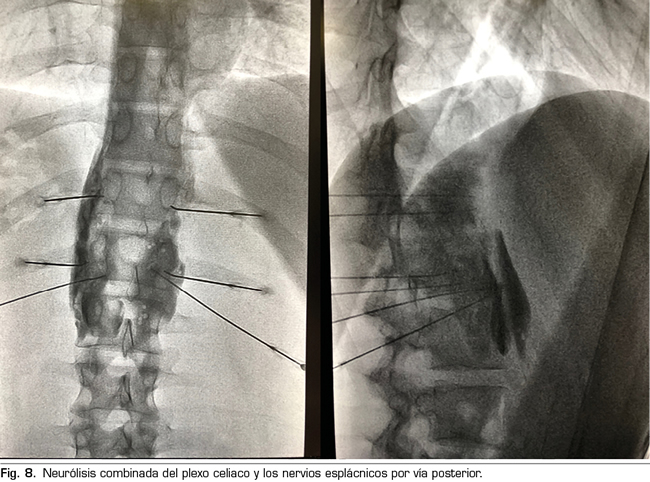

Figura 8